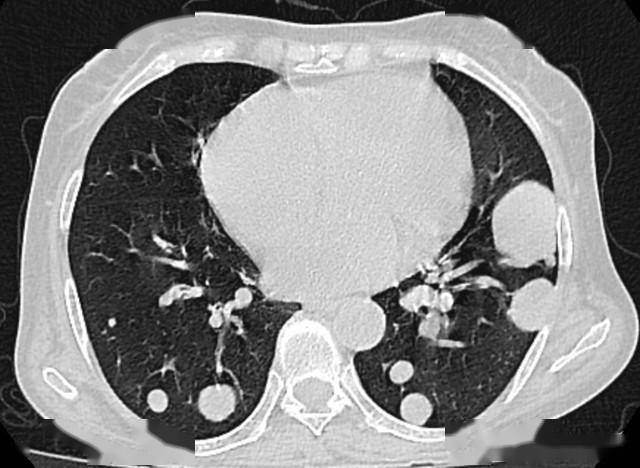

- 定期复查:首次发现结节后,直径<5mm者每年复查1次CT,直径5-10mm者每6个月复查1次,直径>10mm者每3个月复查1次,记录结节变化;